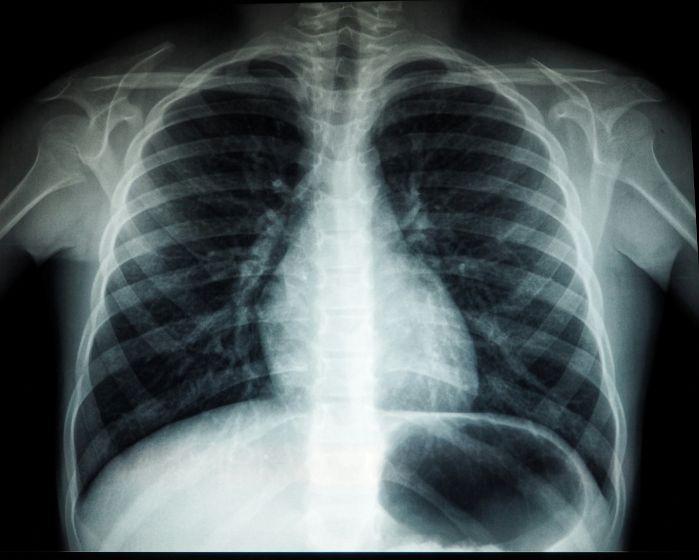

최신 보건 데이터에 따르면 심혈

관 질환은 현재 암에 이어 캐나다

인의 사망 원인 2위를 기록하며 국

민 건강을 위협하는 가장 치명적인

질병으로 확인됐다.

이번 연구를 진행한 전문가들은

현대 캐나다인의 불균형한 식습관

과 신체 활동 부족이 심혈관 질환

발병률을 급격히 높이는 핵심 동력

이라고 지적했다.

가공식품 섭취가 늘어나고 앉아

서 근무하는 시간이 길어지면서 고

혈압과 고콜레스테롤을 앓는 인구

가 전 연령대에 걸쳐 증가하고 있 다는 분석이다. 특히 이러한 기저

질환들이 뚜렷한 전조증상 없이 진

행되다가 갑작스러운 심근경색이나

뇌졸중으로 이어지는 ‘침묵의 살인

자’ 역할을 하고 있다고 경고했다.

연구진은 심혈관 질환의 약 80%

가 적절한 생활 습관 개선만으로도

예방이 가능하다는 점에 주목했다.

나트륨과 당분을 줄인 식단 관리와

주당 최소 150분 이상의 유산소 운 동은 위험 수치를 획기적으로 낮출 수 있는 가장 확실한 방법으로 꼽 힌다. 또한 본인의 혈압과 혈당 수 치를 정기적으로 확인하는 사소한 습관이 치명적인 사고를 막는